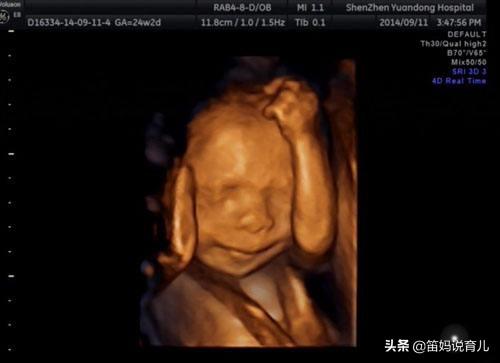

为什么有的人做四维彩超看不到胎儿的五官?

看四维报告单 , 我们会发现 , 上面关于头面部的描述中 , 只有对眼框、鼻、唇部的判定 , 没有耳朵的踪影 。

据医生介绍 , 四维彩超不负责对耳朵、脚趾、手指等部位进行排畸检查 。 但实际上耳朵是能看到的 , 我看很多四维照片上都出现了耳朵 。 负责任的医生也会帮忙看一下不在检查之列的部位 , 但不写到报告单上 。

胎儿体位影响

做四维彩超时 , 宝宝不配合 , 只给一个正面、只给一个侧面、只给一个背面 , 就看不到宝宝的耳朵 。 所以 , 就出现了医生让孕妈妈反复做四维、四维时间长的问题 。

胎儿的身体挡住了耳朵

胎儿在肚子里是经常活动的 , 手舞足蹈起来谁也控制不了 , 所以难免出现肢体挡住耳朵的情况 。 比如宝宝做出双手抱住脑袋的动作 , 这样就把耳朵生生地挡住了 , 怎么也看不到 。

还有的脐带也会挡住宝宝的耳朵 , 所以也有可能看不到 。 如果想看到耳朵就和医生好好说一下 , 或者再做一次 。

耳朵紧贴头部

不知注意到没有 , 孩子出生后 , 耳朵是紧贴在头部的 , 到十几天后才会慢慢舒展开 。 在做四维的时候 , 耳朵也是紧贴在头部的 。 这时候耳朵很小 , 宝宝的头部侧面也不是很规则 , 耳朵就不容易分辨 , 所以是看不清楚的 。

所以 , 医院里有一项规定 , 像耳朵、手指、脚趾这些容易出现误差的部位 , 是不负责判断的 。

总之 , 做四维彩超看不到耳朵的情况是很多的 , 不用担心 , 这种情况的不在少数 。 等宝宝长大一点 , 再去做彩超就会看得更清楚一些 。